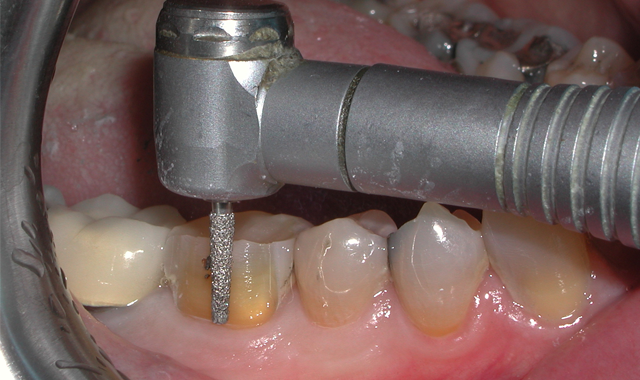

Fig. 4 Fig. 5

The first step in preparation of tooth #30 for a PFM crown is reduction of the clinical crown in the buccal and lingual dimensions. This was accomplished using a flat-ended taper diamond bur (Premier Dental, Solo Diamond #846KR016C) to create rounded internal line angles (Fig. 5).

Next, interproximal contacts are broken using a round end-taper diamond bur (Premier Dental, Solo Diamond #850012C), followed by occlusal reduction and shaping using a football diamond bur (Premier Dental, Solo Diamond #368T023C) (Figs. 6-7). Proper axial reduction for a PFM crown should be 1.0-1.5 mm and occlusal reduction of 1.5-2.0 mm in the central fossa.